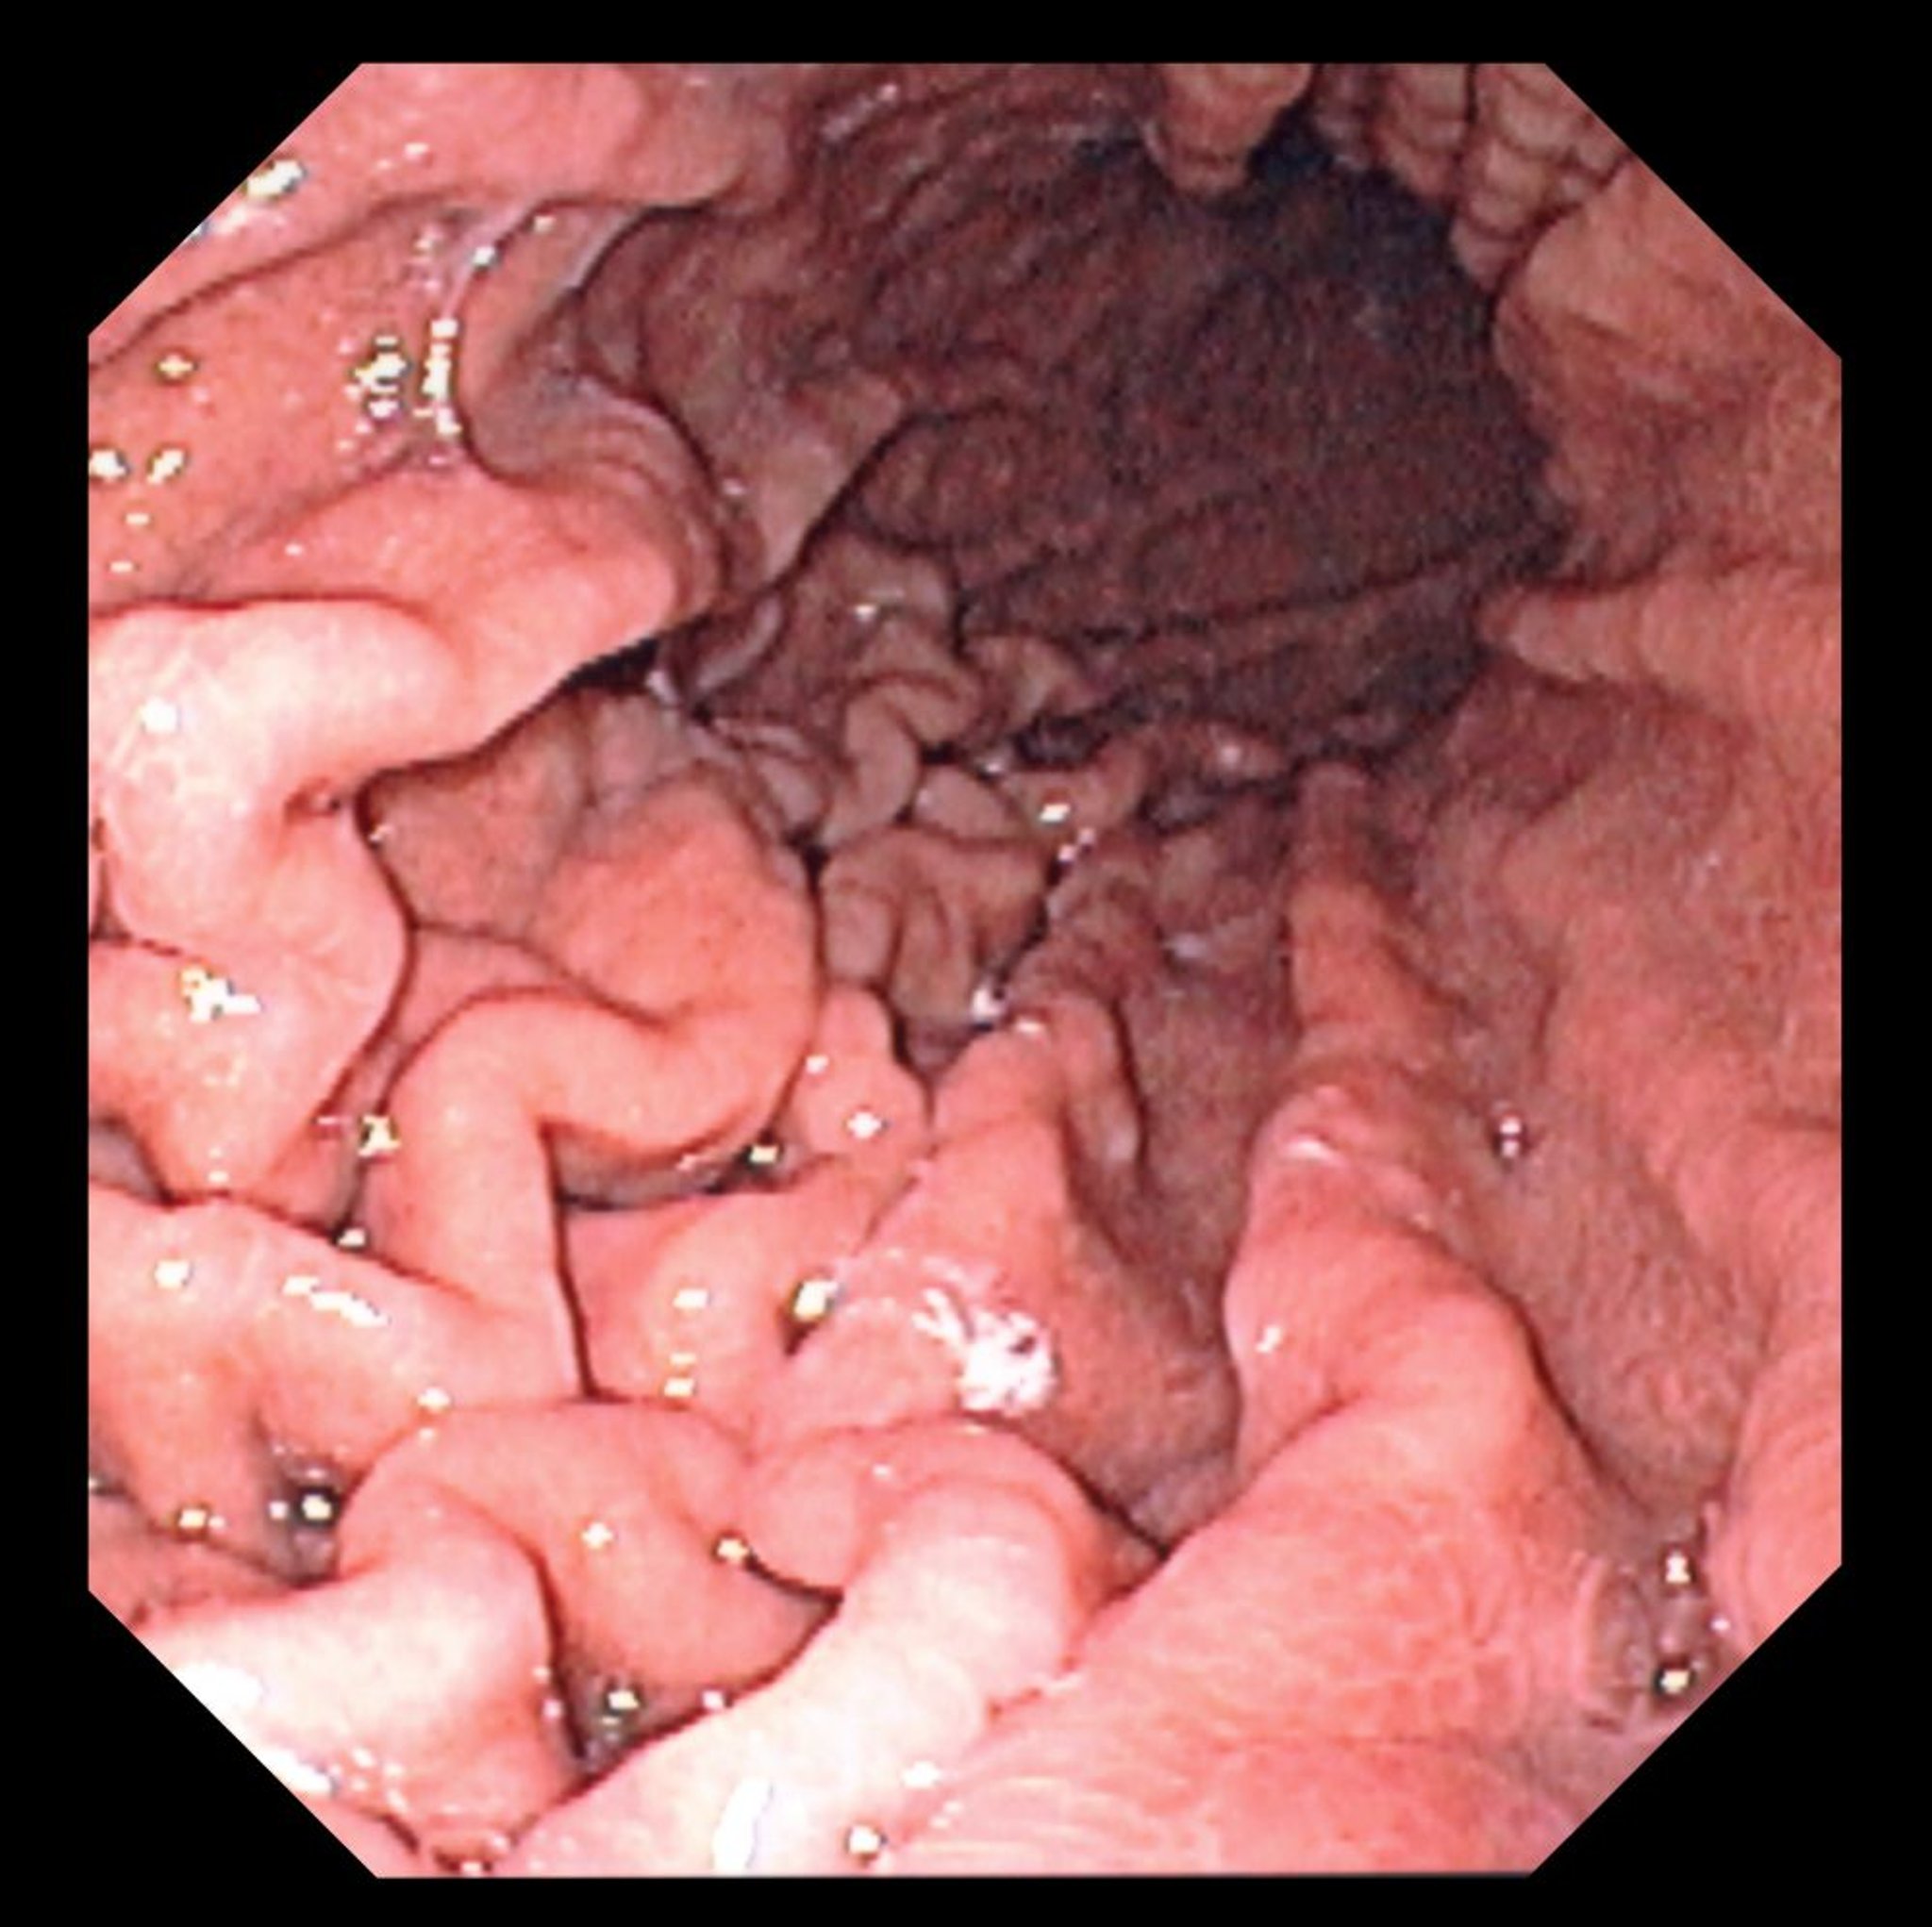

Эта фотография отображает эндоскопическую картину нормального дна желудка с характерными желудочными складками.